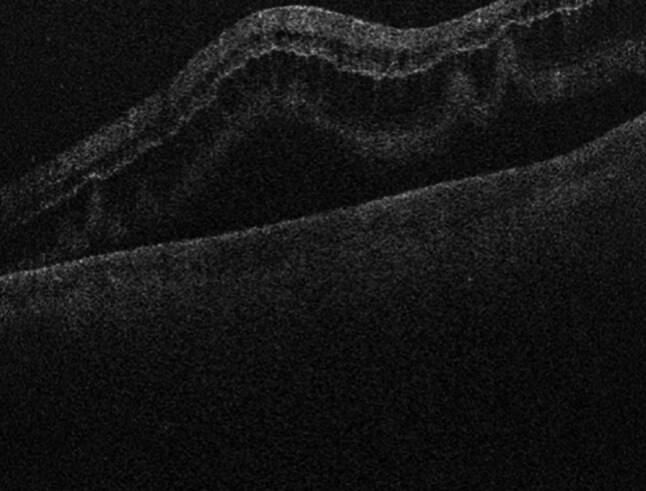

如果不及时治疗,视网膜脱离有可能成为永久性致盲疾病,因此是眼科紧急情况。这篇综述将概述历史,发病机制,临床表现,以及目前和未来的处理视网膜脱离。

Retinal detachments are ophthalmic emergencies given their potential to become a permanently blinding disorder if left untreated. This review will outline the history, pathogenesis, clinical presentation, and current and future management of retinal detachments.